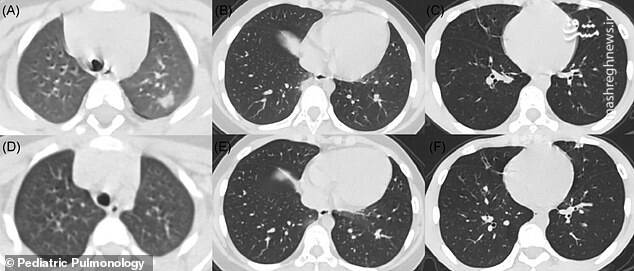

mshrgh.ir/1071375 کد خبر 1071375 تاریخ انتشار: ۲۲ اردیبهشت ۱۳۹۹ - ۰۸:۰۳ ۰ نظر چاپ عکس و فیلم عکس/ سی تی اسکن از کودکان مبتلا به کرونا تصاویر سی تی اسکن از کودکان مبتلا به کرونا در بوستون آمریکا نشان می دهد بیش از نیمی از آنها دچار التهاب شدید ریه هستند. اخبار مرتبط عکس/ تمرین ورزشکار قایقرانی در خانه فیلم/ اروپا در صف کیت تشخیص کرونای ایرانی فیلم/ آخرین آمار مبتلایان به کرونا در جهان عکس/ تمرین ورزشکاران ایرانی در شرایط کرونایی فیلم/ نکات کلیدی استفاده از ماسک در مترو عکس/ درگیری پلیس با مخالفان قرنطینه عکس/ تعظیم تکنولوژی، اینترنت و آموزش مجازی! عکس/ همافزایی گروههای جهادی در پویش ۱۴۴۱ عکس/ دیدار بستگان از طریق جرثقیل عکس/ به وقت افطار عکس/ تظاهرات معترضان به قرنطینه در آلمان عکس/ تب سنجی قبل از جلسه دادگاه عکس/ مقاومت یک کودک در برابر انجام تست کرونا عکس/ مرحله دوم کمک مومنانه در آذربایجان برچسبها ویروس کرونا کودکان سی تی اسکن بیماری ریه آمریکا